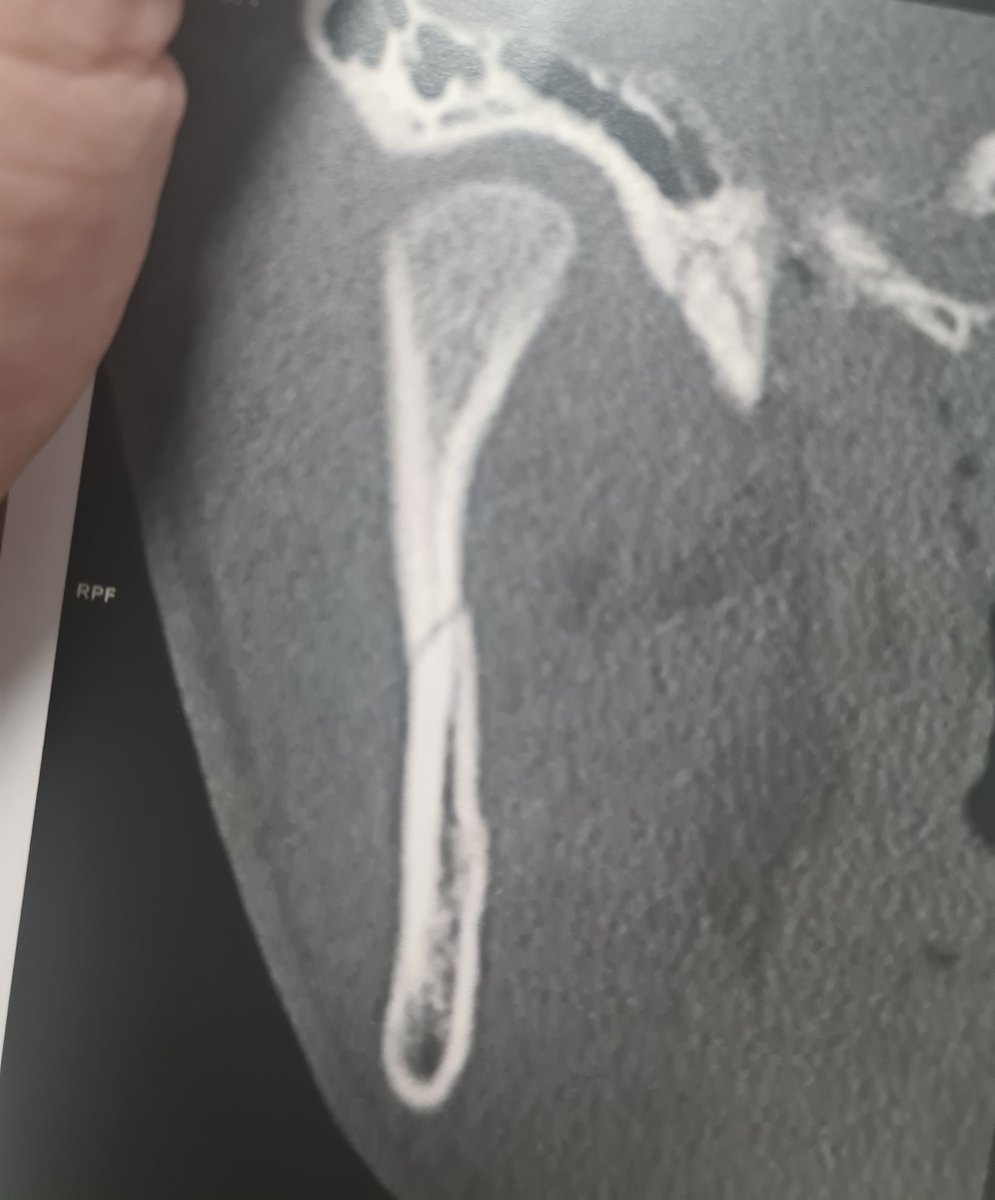

Motif de consultation : "j'ai mal à la mâchoire, là, sous sous l'oreille, depuis une chute y'a quelques jours, j'ai vu l'ostéopathe deux fois, j'ai encore plus mal, je viens vous voir"

Le scanner réalisé en urgence :

1/ Image

La clinique : "je sens moins ma lèvre et mon menton aussi"

La question : "vous aviez cette sensation après la chute ?"

La réponse "non, mais après avoir été voir l'ostéopathe, la seconde fois, quand il y est allé plus fort"

2/